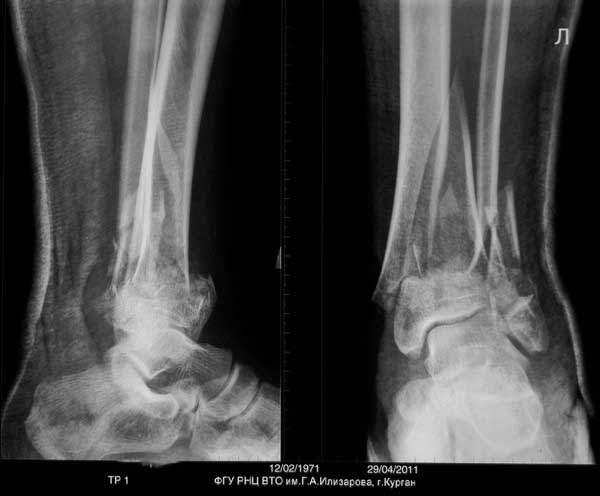

Уважаемый Сергей! Следует уточнить(для уважаемого сообщества) , что переломы находятся на разных конечностях, поэтому восстановление длины бедра потребует равнозначной коррекции длины голени. Либо, как предлагает профессор Djoldas Kuldjanov, не добиваться полной репозиции и пожертвовать частью дистального отломка, сохранив ось и ротацию. Корригировать длину голени проще ввиду меньших усилий по преодолению ретракции мягких тканей. Хотя пациент молодой и желательно наиболее полно восстановить конечности. Несомненно,аппарат Илизарова собирать долго и нудно и неохота, но возможность управляемой фиксации при минимальных экономических затратах перевешивает данные "недостатки". Да и не располагаем АО фиксаторами, гексаподами. Следует учесть и то , что при одномоментной коррекции длины голени (3,5 - 4 см) могут возникнуть трудности с зашиванием и заживлением операционных доступов. Еще позволю уточнить, что клинических признаков консолидации на голени нет - подвижность полная, что не потребует остеотомии малоберцовой кости. Поэтому желаю Вам, Сергей, удачи в одномоментной коррекции деформации бедра и остеосинтезе, но нужно быть готовым к варианту Александра Николаевича - дистрактор, дозированная коррекция смещения по длине, остеосинтез.

Судя по р-грамме, по имеющимуся "облачку" на медиальной стороне, идет консолидция отломков.

Так что - только открытое, одномоментное выправление. Осторожненько поработайте распатором, освобождая от мозоли (лучше используйте круглый распатор Кобба!) и медленно растягивайте на дистракционном ортопедическом столе, под контролем ЭОП-а.

По поводу голени, вариант "улучшить стояние костных отломков" открытым методом - немного рискованно, потому что результат манипуляции "распатором Кобба" с дескелетизацией фрагментов скажется немедленно. Для предупреждения осложнений и будущих дисскуссий “как победить сегментарную дефект”, желательно работать без интервенции на начавшийся репаративный процесс с максимальным сохранением костной мозоли.

Для максимального сохранения консолидации сверху мозоли можно согнуть пластину, но это крайняя мера и не обязательно подгонять показания под имеющийся имплантат. Если не удовлетворяет положение, или неполная консолидация, вместо пластины можно применить отечественный аппарат Илизарова. Спросите у докторов Соломина или Мацукатова, и они подскажут методы исправления деформации собственными "гексаподами".

Для оценки степени сращения костей голени рекомендуется сделать КТ срезы. И возможно, для голени не надо предпринимать ничего. Там процесс консолидации заканчивается, и хотя форма далека от идеала, но не так уж плоха. Уже время для нагрузки, и дайте возможности нагружать! Время покажет, и в зависимости от активности в дальнейшем можно обсудить план лечения в будущих дисскуссиях.